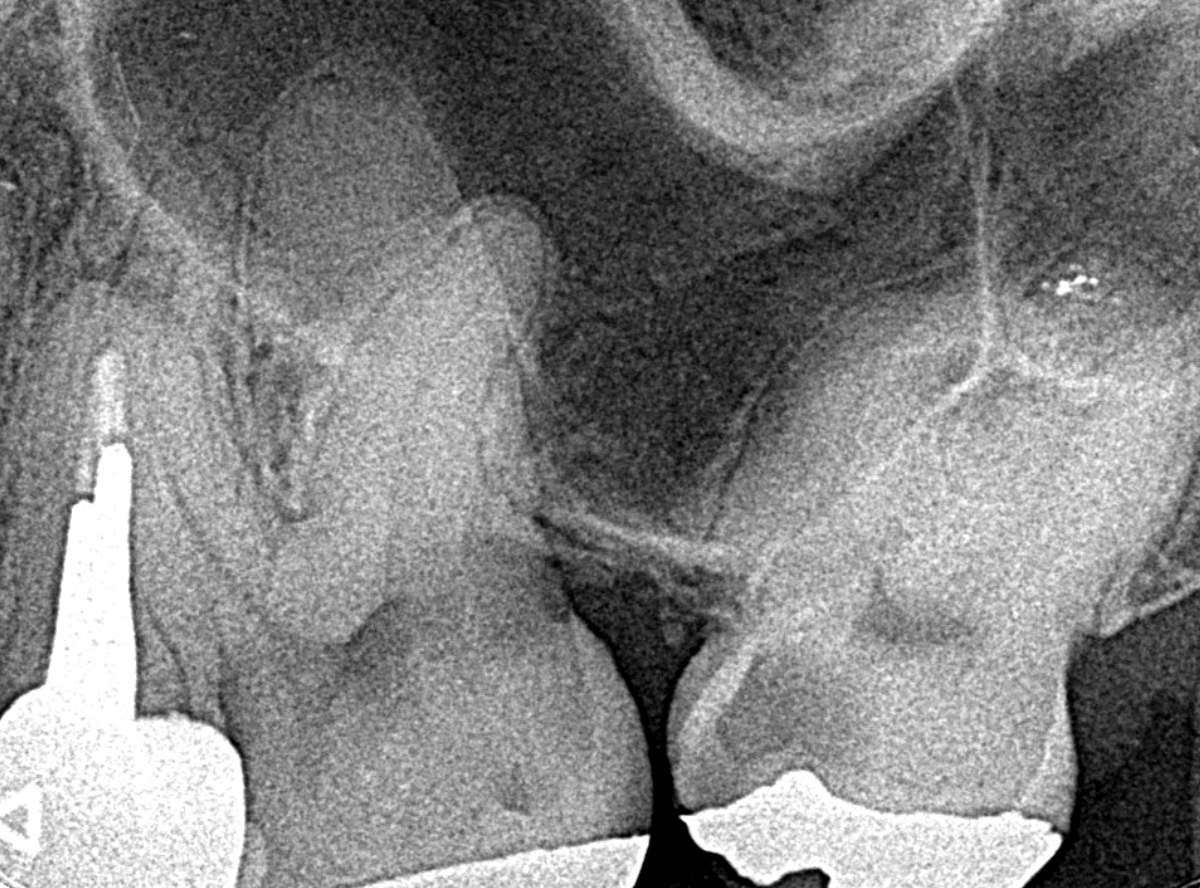

Case.14 インレーの下の歯肉まで広がった虫歯

「下の奥歯が噛むと痛む」という症状で来院された患者さんのケースです。

お口の中の状態を確認すると、奥歯の端に穴が開いているのが見えます。

ここかな?

レントゲン写真で確認します。

やはり、奥歯の端が大きな虫歯になっています。

青いラインが歯の神経、赤いラインが虫歯です。

レントゲン写真上では虫歯が神経まで達しているように見えます。

これは、神経を取らないとダメかもしれません。